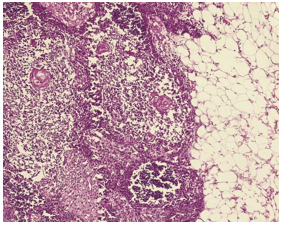

Figure 6: Histopathology of Mass (Thymolipoma).

Figure 7: Mature adipose tissue admixed by normal thymus containing epithelial cells, thymic lymphocytes and Ha.

There were also foci of collagenous fibrosis and accumulation of cholesterol crystals. No signs of malignant disease were observed. Final pathologist report was thymolipoma. The patient remains asymptomatic during sixmonth follow-up.